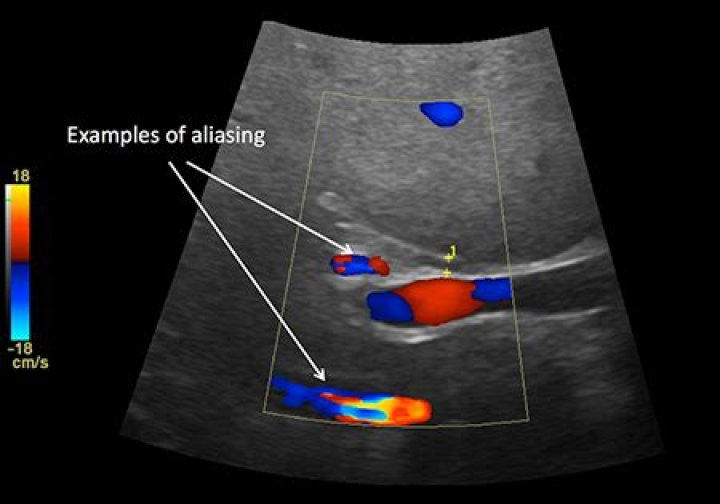

In sonographic. Doppler, the result of aliasing is an apparent change in direction of blood flow in. high-velocity areas, producing flow that appears to be backward. Aliasing can occur in pulsed and color Doppler; continuous-wave.

Aliasing is a phenomenon inherent to Doppler modalities which utilize intermittent sampling in which an insufficient sampling rate results in an inability to record direction and velocity accurately.

Aliasing is a phenomenon in pulsed Doppler echocardiography in which when the velocity is beyond a particular limit known as the Nyquist limit, the direction of flow is depicted as opposite to that of the actual one.

Most sonographers encounter aliasing with pulse spectral Doppler or color Doppler. Pulsed ultrasound doesn’t have a particular upper limit for displaying the Doppler shift. It’s commonly known as the Nyquist limit. High-velocity blood circulation causes Doppler shifts beyond the Nyquist limit resulting in aliasing.

Aliasing phenomenon is a concept that causes a lot of uncertainty for many of us. … We see examples of aliasing in both colour and spectral Doppler, where the velocity exceeds the Nyquist Limit and the image displayed would suggest flow is heading in the opposite direction.

Aliasing. Aliasing arises when the Doppler shift of the moving blood is higher than half of the PRF (Nyquist limit). Aliased signals are displayed with the wrong direction (red instead of blue and vice versa) and velocity (the hue of the colour) (Fig.